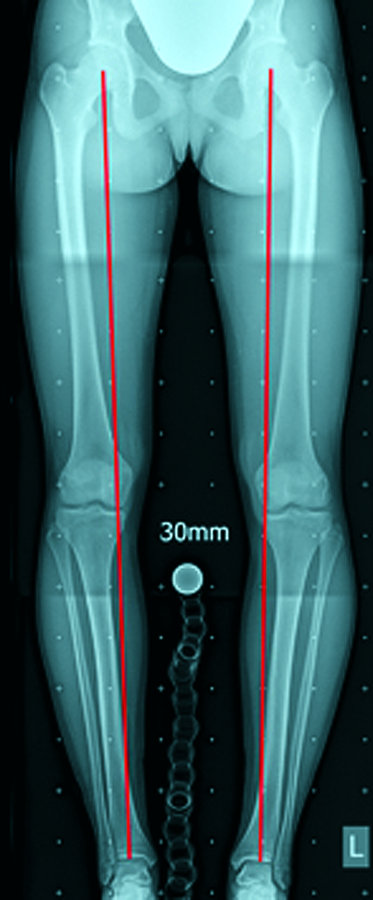

Trotz Trainingspause klagte diese 17-jährige Fußballerin seit sieben Monaten über Knieschmerzen beidseits. Das Röntgen zeigte deutlich O-Beine. Trotz Trainingspause klagte diese 17-jährige Fußballerin seit sieben Monaten über Knieschmerzen beidseits. Das Röntgen zeigte deutlich O-Beine. © Arbeitsgruppe 3D-Chirurgie